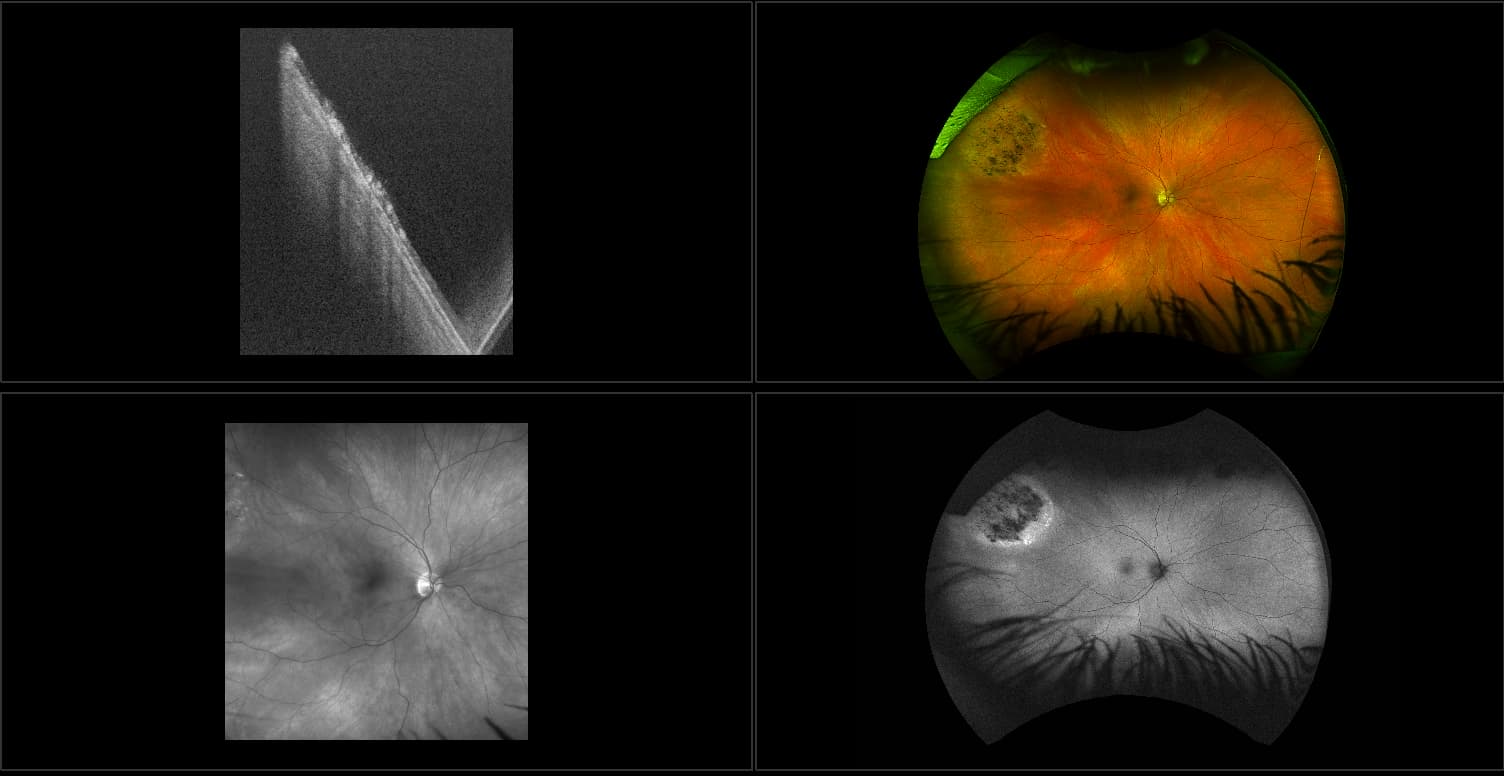

California - Choroidal Nevus, RG, AF

A choroidal nevus is simply an accumulation of melanocytes in the choroid. They are a space occupying mass or a benign melanoma. Choroidal nevi are slate gray in color, have indistinct margins, and may be slightly elevated (1-2 diopters). Since they are in the choroid, they are usually only seen in the red separation and not the green. The green separation may show the RPE degeneration associated with nevi which is seen as pigment mottling and drusen.